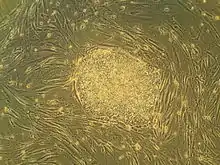

A colony of human embryonic stem cells